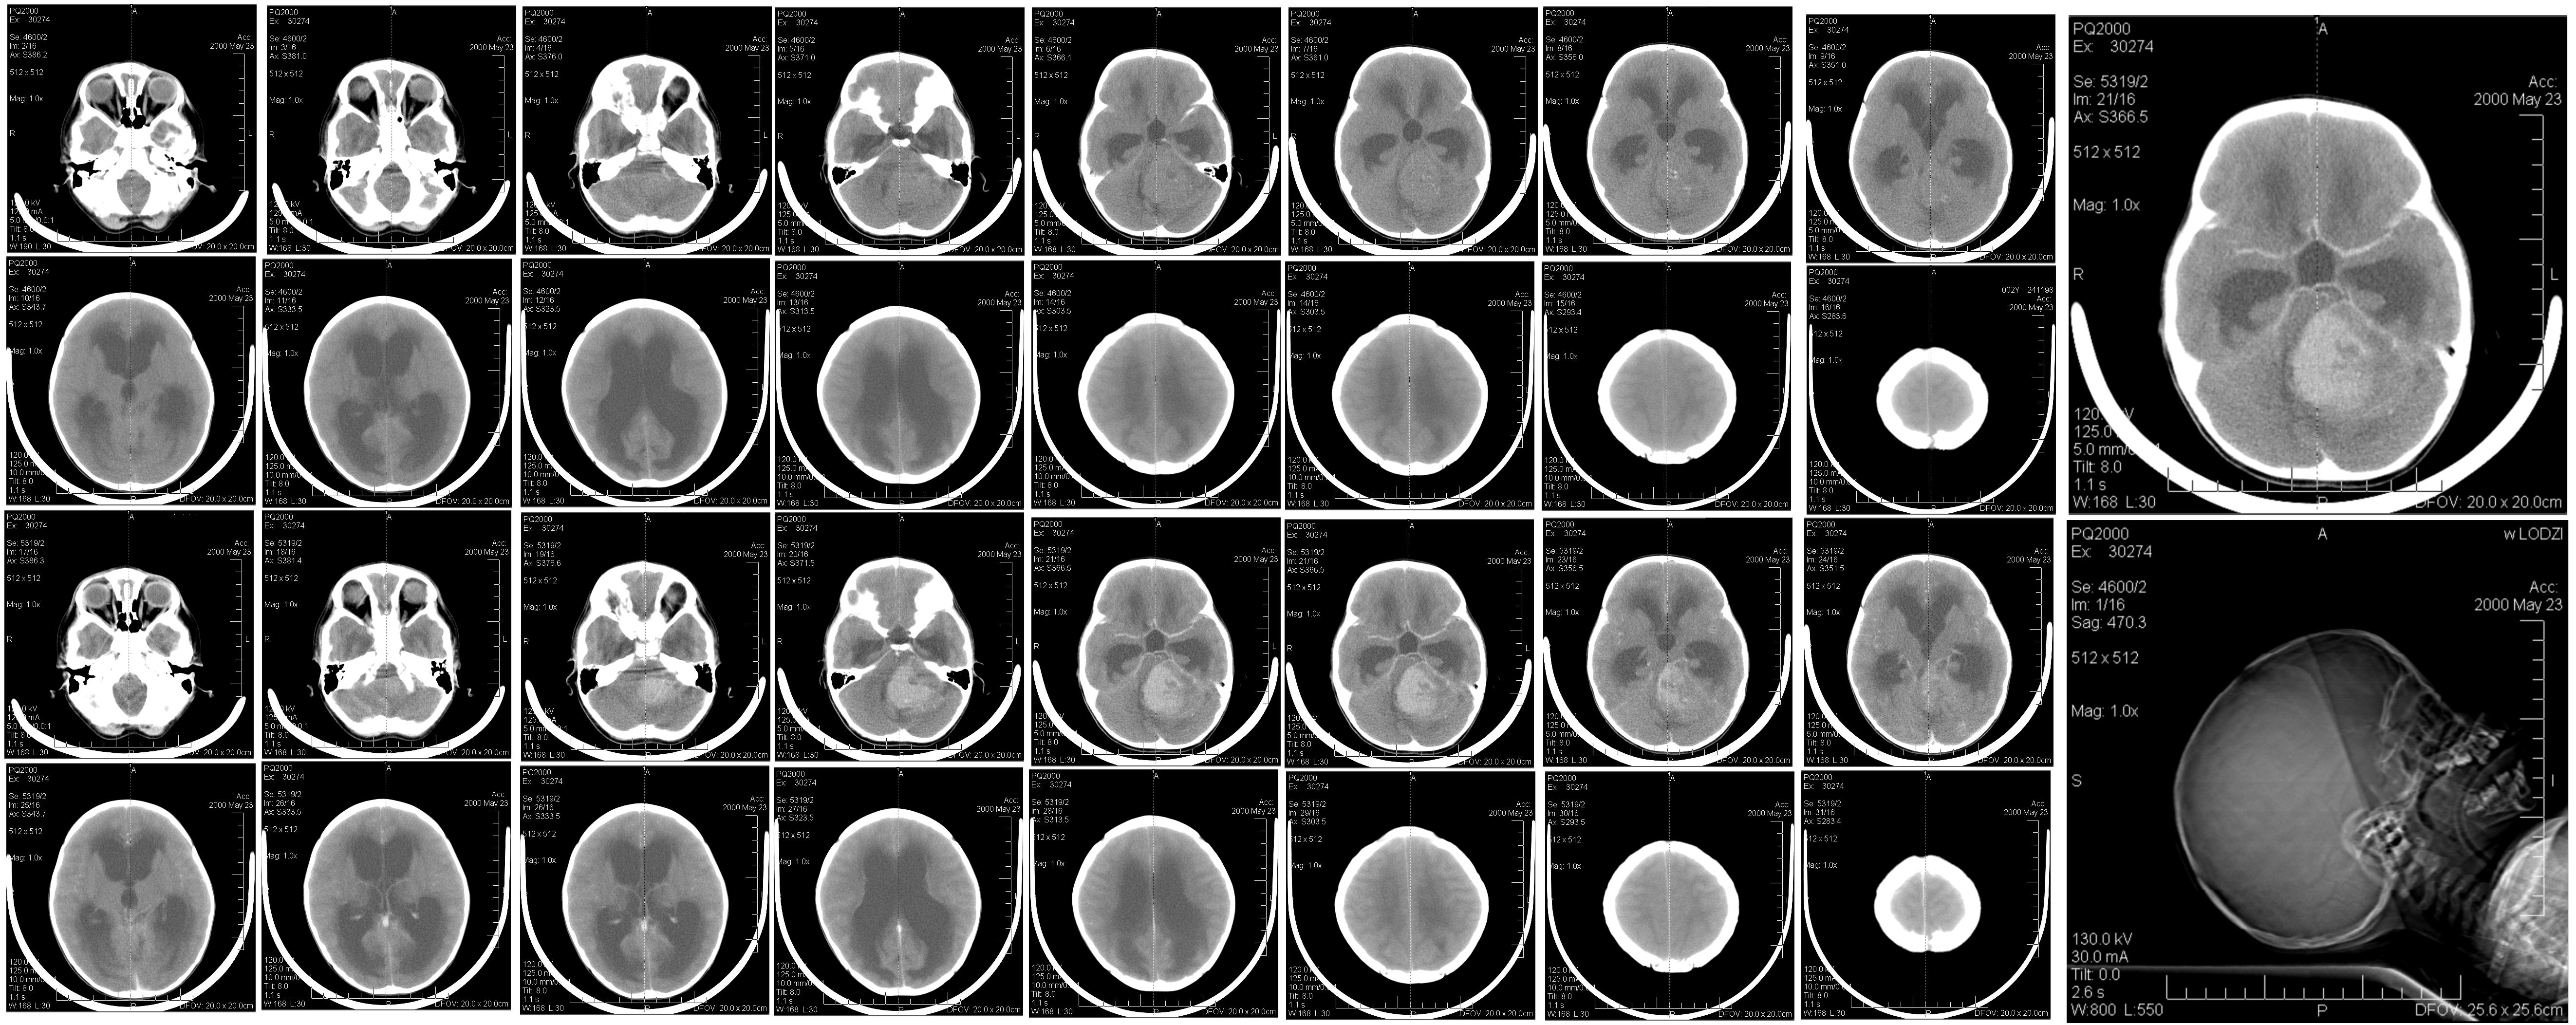

Previously, we saw that imaging and treatment have distinct goals and distinct demands on the type of radiation used. We’ve also established that the X-ray is currently the default modality for both imaging and treatment. In treatment, as well as diagnosis, an accurate view of the patients internals is required, and this view is obtained with

CT. This method makes use of the fact that different tissues have different X-rays absorbtion coefficients. Imaging is a collective term for any and all types of images, including simple ‘photographs’. A CT scan composites multiple flat images into a 3D model, in which certain tissues are identified and optionally highlighted and viewed in the direction that is desired (figure 10).

The hadrons themselves could be tracked and absorbed in order to create an image. Using energies higher than for therapy, placing the Bragg peak behind the body, the ionizing damage could be minimized further. Apart from sparing tissue compared to X-ray irradiation (figure 1), there is a second benefit to hadrons for imaging: an increased density resolution in comparison to X-rays. Figure 11 shows how Ryu et al. (2008) makes that clearly visible. More contrast is seen between the different types of material, and, using different calibration curves, the contrast may be adjusted as a doctor sees fit. Also visible is the difference in sharpness: because protons scatter much more than photons, the precision in the plane perpendicular to the beam is lower. For imaging, it seems hadron-CT could augment the γCT in the depth dimension. Moreover, conversion of radiodensity of the different modalities (γCT Hounsfield numbers versus hadron stopping powers) is a relatively imprecise method, introducing an error of up to 3% (Penfold et al., 2009). Using hadron data sidesteps this problem completely. Producing usable hadron images therefore is desirable even if they will not be used for diagnosis.

Going from simple 2D projections to a fully reconstructed CT scan is a nontrivial matter, so let us start with the simple case of the 2D image. For every pixel one residual intensity value is measured, and therefore the opacity of the body is summed over all tissue behind that pixel. The spatial distribution in the depth direction is therefore lost. An accurate 3D model reconstruction would aid in the establishment of opacity, and thus radiodensity, for each volume element. The radiodensity is tissue-specific, so full knowledge of spatial distribution in the depth direction would be reconstructed and the structure of the the patients body would be known. With conventional X-ray imaging, the common geometry in γCT is a camera rotating about an axis parallel to the length of the patient. A series of 1D line integrals are obtained by moving the camera around the patient. As the camera moves along the body, new sets of 1D line integrals are obtained, each corresponding to a slice of tissue: tomography. The line integral of the absorption is now known for many different positions and angles, and the reconstruction software reconstructs for each voxel in a slice the local absorption coefficient, resulting in a 2D image: computed tomography. These typical 2D 30cm squared images are what most doctors are used to. As available computational power increased, the 3D reconstruction of the body in the detection volume became possible. For hadron CT, or pCT, as protons are the most commonly used hadrons, rotating the camera and the beam around the patient requires an expensive gantry. An extra constraint for pCT could therefore be that algorithms work well without a gantry; it can cope with images from a reduced number of angles. One could consider changing the position of the patient table instead of the gantry.